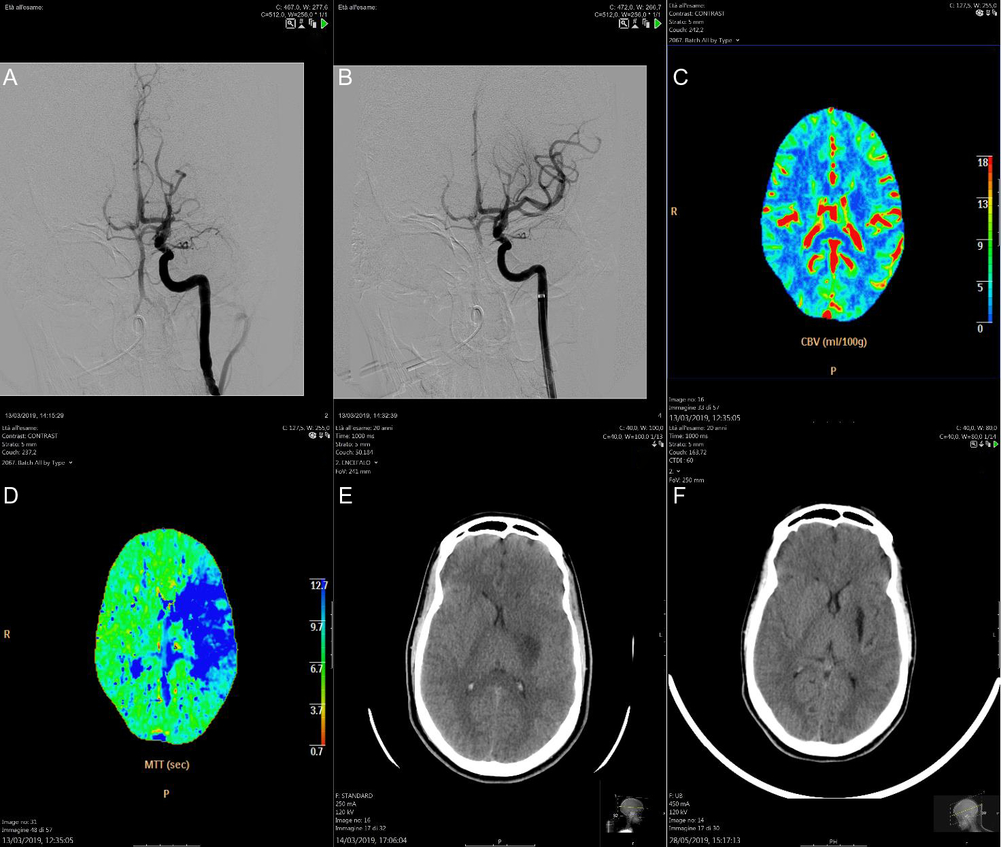

The second case is a late teenage patient, with limb-girdle muscular dystrophy (LGMD) associated with hypertrophic/dilated cardiomyopathy that had required an implantable cardioverter defibrillator (ICD). She was admitted to our hospital for right hemiparesis and aphasia (NIHSS 9) on awakening. Because of her ICD, cerebral MRI could not be performed. An emergency CT angiography revealed occlusion of the left M1 segment of MCA (Figure 2A); a hypoperfused region of the brain with favorable mismatch were detected on perfusion imaging in the territory of the left MCA (Figure 2C,D). Thrombectomy was performed using a stent retriever. After a single pass, the clot was completely removed and the flow in the M1 was completely restored, resulting in a TICI III (Figure 2B). The next day, cerebral CT scan showed an infarction in the left lenticular nucleus and in the posterior corona radiata (Figure 2E). Cardiac monitoring identified atrial fibrillation (AF). The patient was discharged with final NIHSS 0 and mRS returned to 1 such as her pre-stroke mRS related to LGMD.

Figure 2: Cerebral angiography revealed occlusion of the left M1 segment of MCA (A); after the thrombectomy, the clot was completely removed and the flow in the M1 was completely restored, resulting in a TICI III (B); cerebral perfusion CT detected a hypoperfused region of the brain with favorable mismatch in the territory of the left MCA (C and D); the next day, cerebral CT scan showed an infarction in the left lenticular nucleus and in the posterior corona radiata (E); after 2 months, the ischaemic lesion became more evident and hypodense on the cerebral CT scan (F).